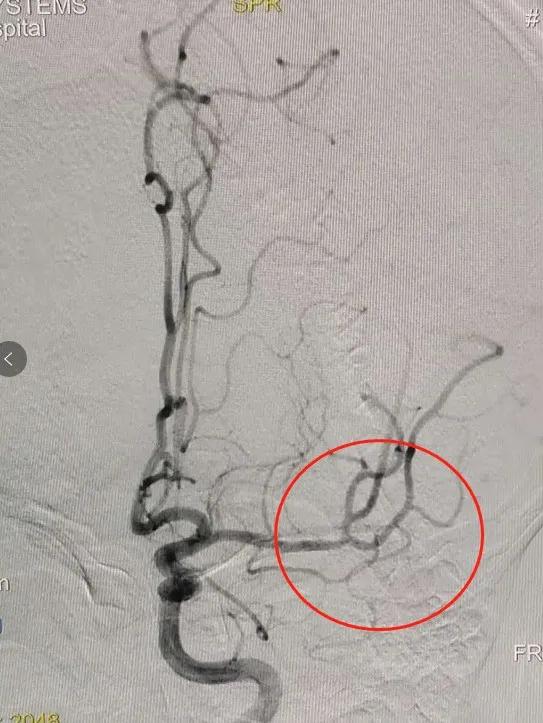

▲脑血栓位置 手术前

▲手术后